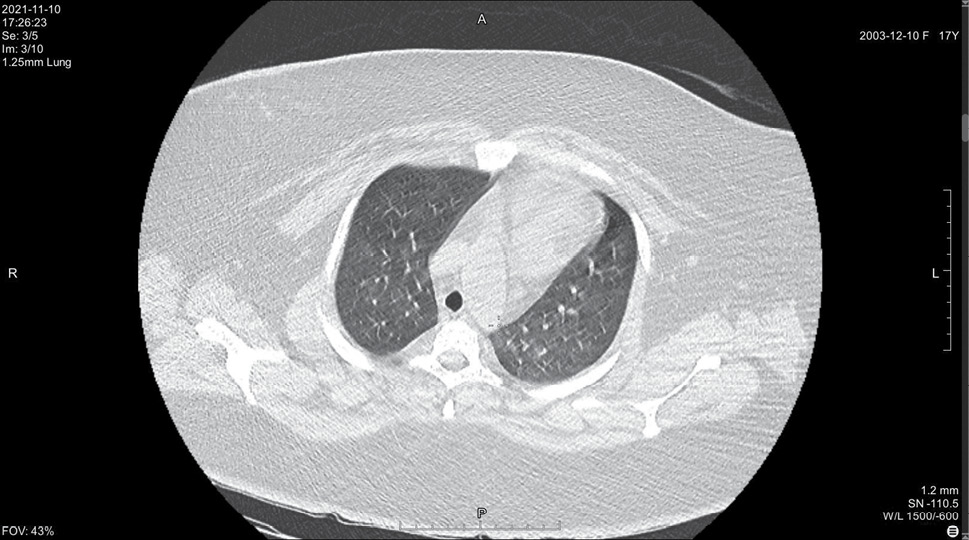

На 14 день болезни (10.11, 7 день госпитализации) была выполнена спиральная компьютерная томография грудной клетки, где выявлены признаки двусторонней интерстициальной полисегментарной пневмонии (рис. 1–8). Форма грудной клетки описана как обычная. Легочные поля расправлены. На томограммах бронхиальное дерево визуализировано до субсегментов: сами бронхи не деформированы, их просвет в пределах нормы, устья свободны, проходимость сохранена на всем протяжении. Во всех сегментах с обоих сторон определялись полиморфные, сливные участки уплотнения легочной ткани по типу матового стекла с участками консолидации. На этом фоне были видны просветы бронхов. Определялись фиброзные тяжи в проекции апикальной плевры обоих легких. Контуры диафрагмы четкие, синусы свободные, свободная жидкость в плевральной полости отсутствовала. Трахея обычной формы и размеров, карина острая. Сосудистые структуры верхнего средостения с четкими контурами и нормального диаметра, стенки сосудов без кальцинатов. Медиастинальные лимфоузлы и лимфоузлы корней обоих легких (без контрастного усиления) визуализированы единично, не увеличены. Сердце расположено обычно, размеры в пределах нормы. Выявлены умеренные дегенеративно-дистрофические изменения грудного отдела позвоночника. Мягкие ткани грудной клетки без особенностей. По заключению врача-рентгенолога, объем пораженной легочной паренхимы достигал 95%. Наиболее вероятно, что патологический процесс у пациентки имел вирусную природу.

Рисунок 1. Томограмма легких на уровне ThIII

Рисунок 2. Томограмма легких на уровне ThIV

Рисунок 3. Томограмма легких на уровне ThV

Рисунок 4. Томограмма легких на уровне ThVI

Рисунок 5. Томограмма легких на уровне ThVII

Рисунок 6. Томограмма легких на уровне ThVIII

Рисунок 7. Томограмма легких на уровне ThIX

Рисунок 8. Томограмма легких на уровне ThX